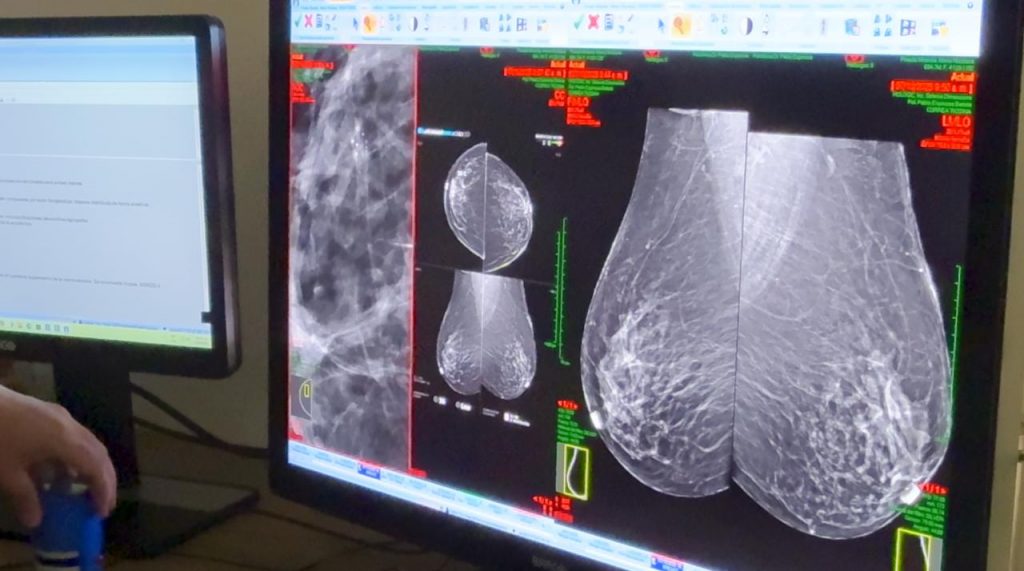

Para las biopsias se emplean dos modalidades: ultrasonido y un mamógrafo de alta tecnología 3D, especializado y asistido por un sistema al vacío, que utiliza agujas especiales para extraer muestras que luego son enviadas al patólogo para determinar la presencia o ausencia de cáncer.